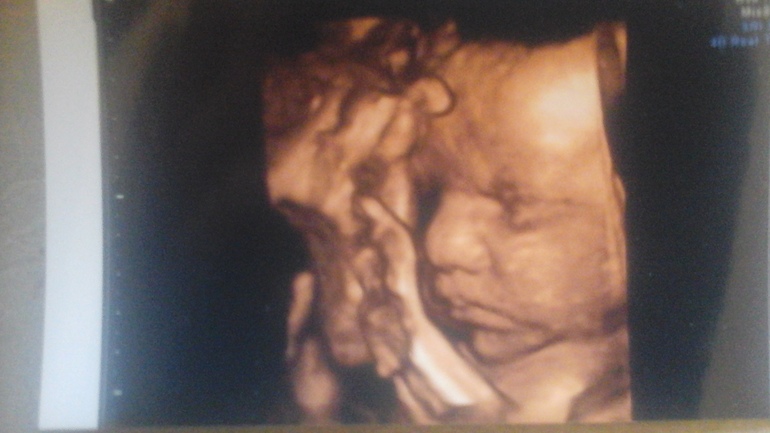

Тазовое предлежание плода.

Вопросы о КСДевочки, у меня вопрос... Заключен договор на пкс, вчера отправила результаты 3 скрининга своему врачу, а он пишит: еще и тазовое предлежание. Я: это очень плохо? Он: с рубцом на матке 100% кс Вопрос: а что при тазовом предлежании кс проходит как то по другому? Или сложнее? Все остальное в норме, рубец 5мм.